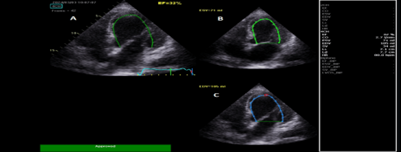

Echocardiography done urgently, while patient was receiving inotropic support, and showed a reduced LVEF at 19% (Figure 3).

Figure 3: A: Apical 4 chambers view showing automatic left ventricular ejection fraction at 19%. B: LV end systolic volume at 66ml. C: LV end diastolic volume at 81ml.

LA=left atrium; LV=left ventricle; RA=right atrium; RV=right ventricle; EF=ejection fraction; ESV = end systolic volume; EDV = end diastolic volume.

After the 4th day intravenous calcium gluconate was stopped and patient was started on oral calcium carbonate (Caltrate) at a dose of 600mg every 6 hours orally with 1,25 hydroxy vitamin D (One-Alfa at a dose of 1 microgram daily orally) with a target Calcium level at 8-8.4mg/dl; also, intravenous furosemide was changed to oral furosemide at a dose of 100 mg orally daily. Repeat echocardiography after extubation and after weaning off inotropes showed an improvement in LVEF at 32% (Figure 7).

Figure 7: A: Apical 4 chambers view after correction of hypocalcemia showing a left ventricular ejection fraction at 32%. B: LV end systolic volume at 71ml; C: LV end diastolic volume at 105ml

LA=left atrium; LV=left ventricle; RA=right atrium; RV=right ventricle; EF=ejection fraction; ESV=end systolic volume; EDV= end diastolic volume.